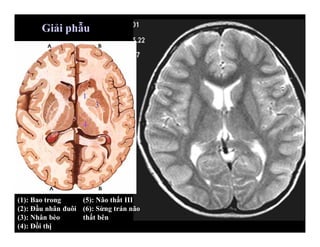

Giải phẫu hình ảnh sọ não

(1): Bao trong

(2): Đầu nhân đuôi

(3): Nhân bèo

(4): Đồi thị

1

2

3

4

5

6

(5): Não thất III

(6): Sừng trán não

thất bên

Giải phẫu